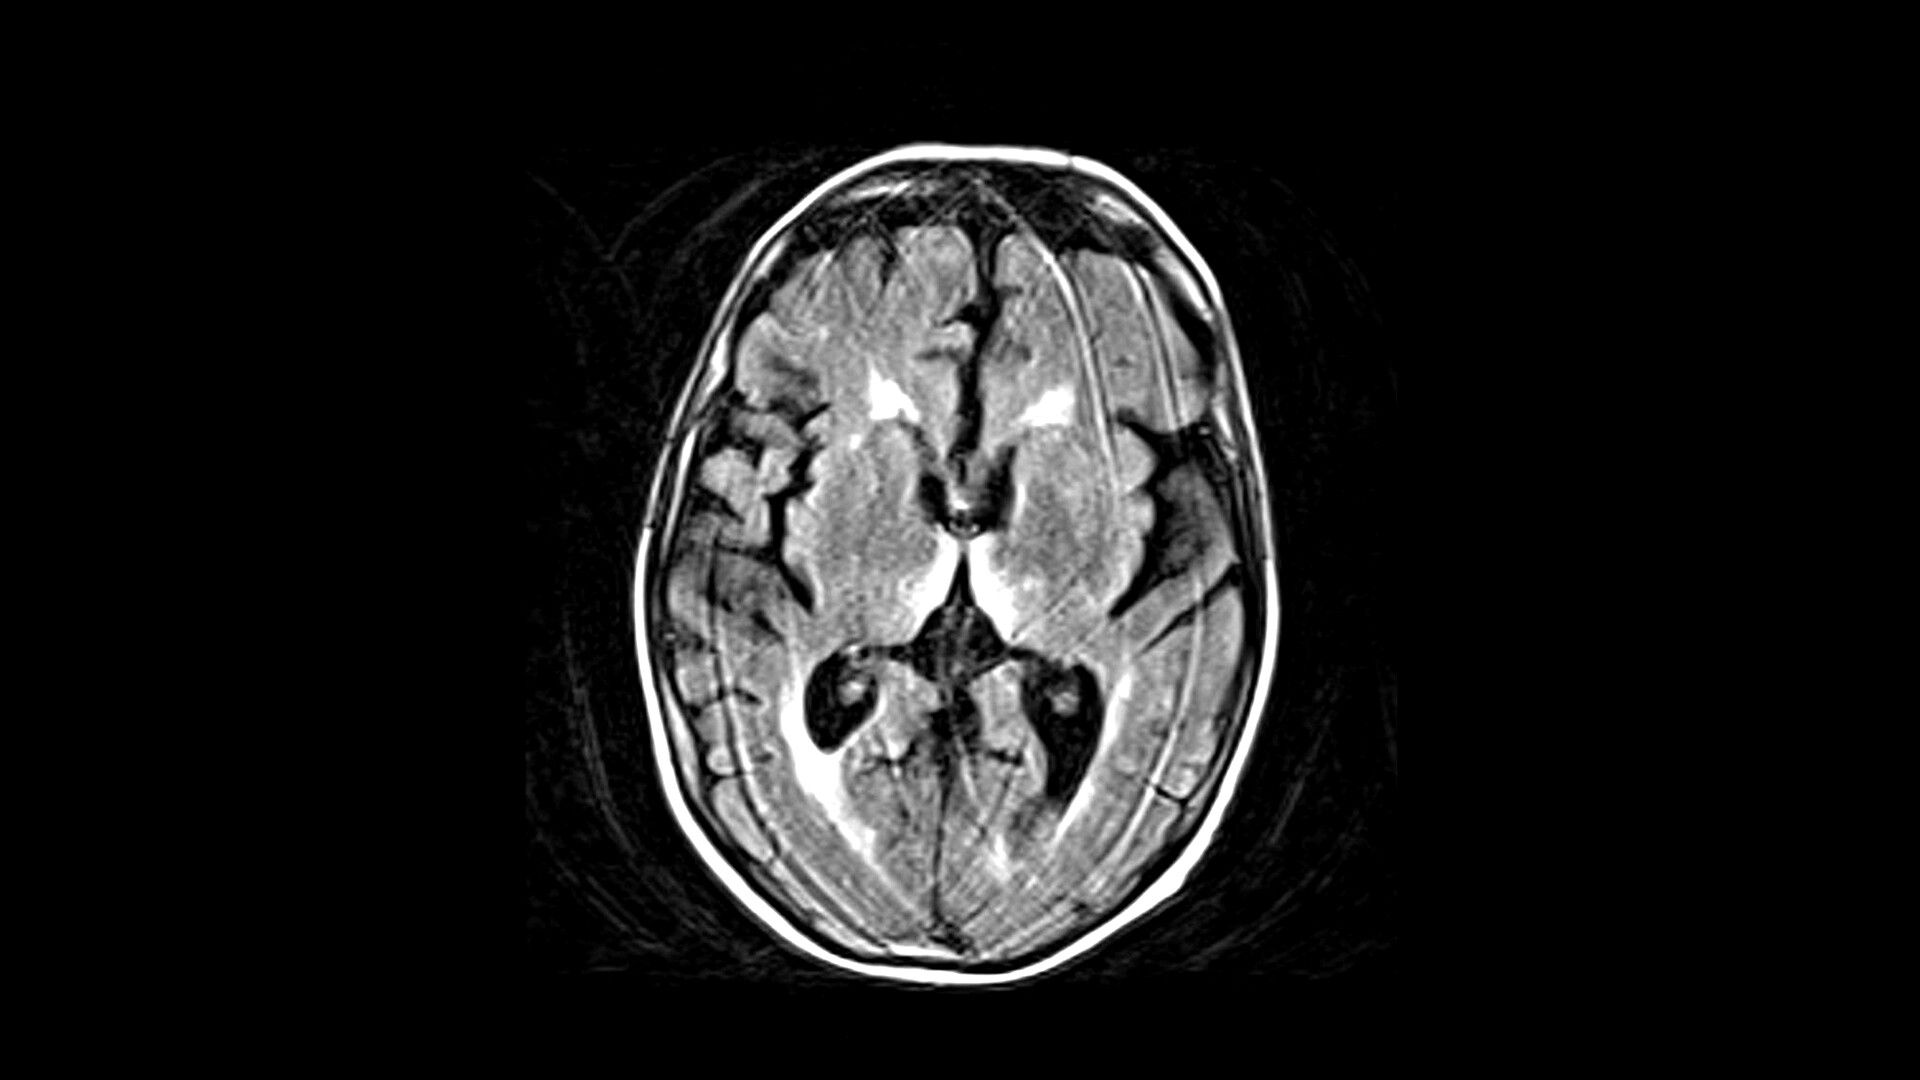

Вернике мрт

Вернике мрт 113 фото